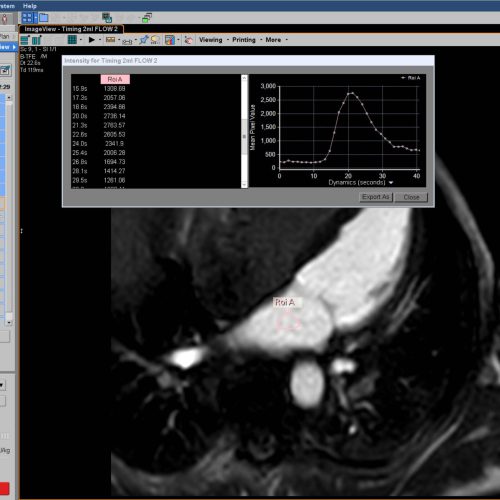

Ein Bolustiming bestimmt die Ankunftszeit des Kontrastmittels im linken Vorhof

Mit einem Bolus-Timing (2ml Kontrastmittel) in der 4-Kammer-Ebene lässt sich die Zeit messen, die das Kontrastmittel braucht bis es im linken Vorhof ankommt.

Das ist genau der Moment, wo sich die Lungenvenen am besten darstellen lassen.

Mit einer kleinen Auswertung an der Konsole wird ein ROI in den linken Vorhof gelegt und in der Grafik/Liste lässt sich die gewünschte Zeit ablesen.